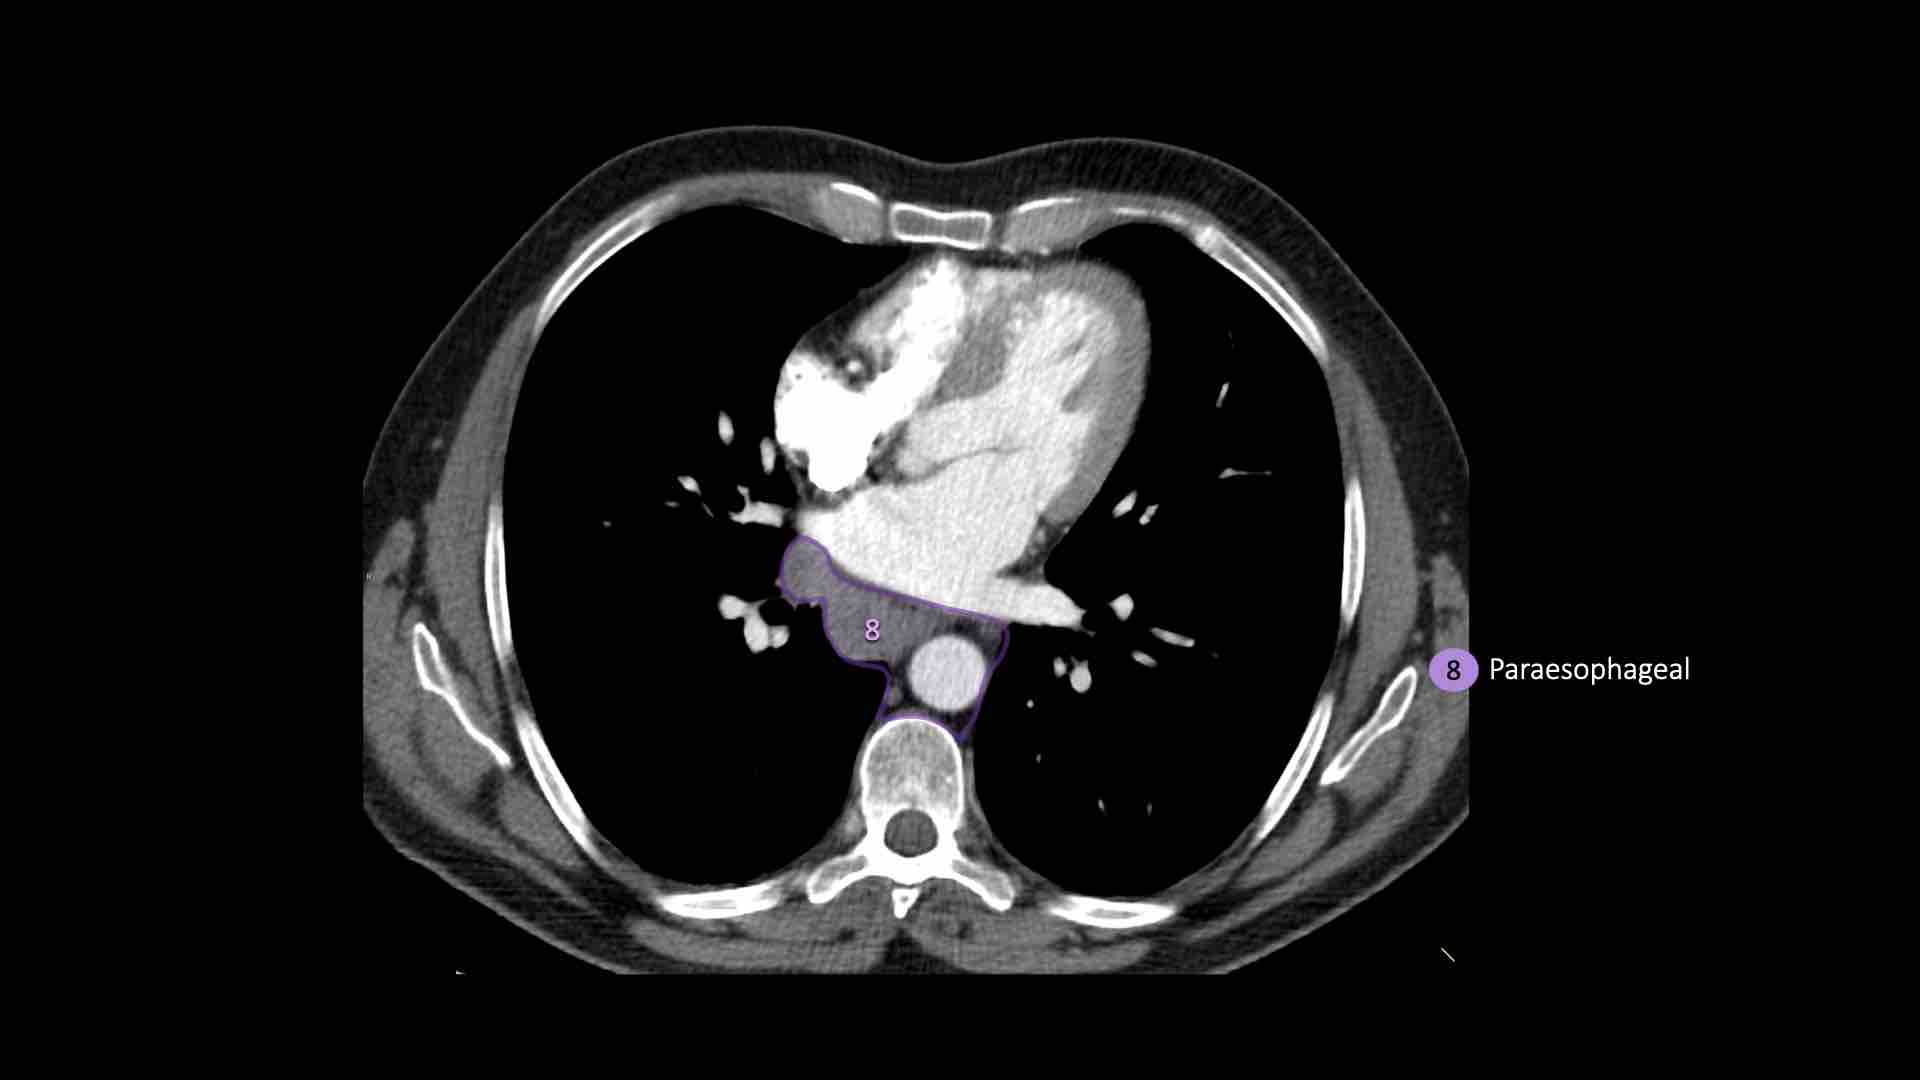

8. Cạnh thực quản

Các hạch nằm dưới carina.

8. Hạch cạnh thực quản

Các hạch này nằm bên dưới các hạch dưới carina và trải dài xuống đến cơ hoành.

Bên trái là hình ảnh dưới mức carina.

Bên phải thực quản là một hạch nhóm 8.